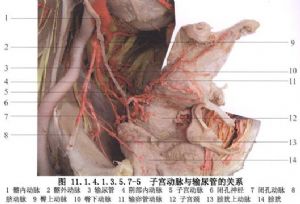

11.5 5.處理韌帶及子宮血管

根據病情切斷、縫扎圓韌帶、骨盆漏斗韌帶、子宮動靜脈,留結紮線牽引(圖11.1.4.1.3.5.7-14)。